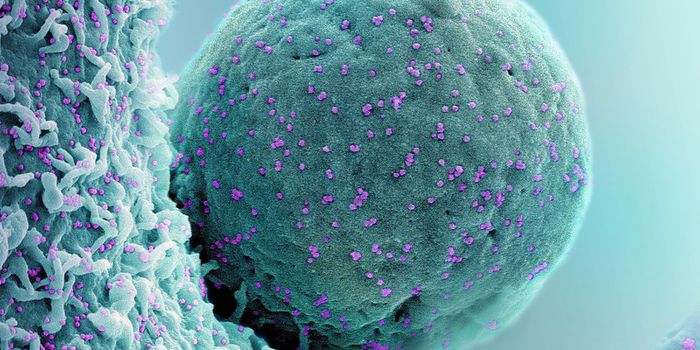

MAY 23, 2024MicrobiologyWhen human immunodeficiency virus (HIV) emerged and was identified as the cause of acquired immunodeficiency syndrome (A ...